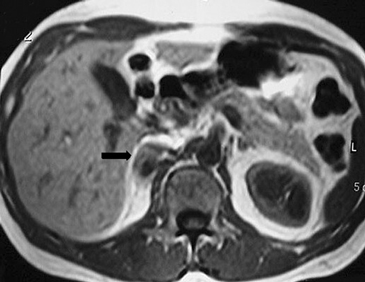

En la TC no contrastada las glándulas suprarrenales normales son homogéneas y simétricas, con una densidad muy similar a la del parénquima renal adyacente (Figura 1 a). Con un medio de contraste ev la glándula suprarrenal se opacifica en forma homogénea, similar al hígado o al bazo (Figura 1 b). Si la cantidad de tejido adiposo retroperitoneal es abundante las glándulas suprarrenales pueden aparecer enteramente rodeadas por grasa y su delimitación es más fácil (Figura 2 a); lo inverso ocurre en pacientes muy delgados con escasa grasa retroperitoneal (Figura 2 b). En RM, en secuencias ponderadas en T1 y T2 convencionales tienen una intensidad de señal homogénea, hipointensa respecto de la grasa adyacente e iso o hipointensa con respecto del parénquima hepático (Figura 3 a y b). En los cortes coronales se aprecia mejor la forma y la posición de las glándulas suprarrenales (Figura 3 c).

Figura 1. Glándula suprarrenal normal en tomografía computada. Cortes axiales de tomografía computada, donde se identifica la morfología normal de la glándula suprarrenal derecha (flecha) en fase no contrastada (a), y tras el uso de medio de contraste endovenoso (b).

Figura 3. Glándula suprarrenal normal en resonancia magnética. (a) Cortes axial ponderado en T1 la señal de la glándula normal (flecha negra) es hipointensa respecto a la grasa retroperitoneal e isointensa respecto al parénquima hepático. (b) Cortes axial ponderado en T2 en que se muestra la glándula suprarrenal derecha (flecha blanca) y (c) corte coronal ponderado en T2 en que se muestra la glándula suprarrenal derecha (flecha blanca) y la glándula suprarrenal izquierda (flecha negra) con similares características de intendidad de señal. 3. Causas y prevalencia de las lesiones suprarrenales